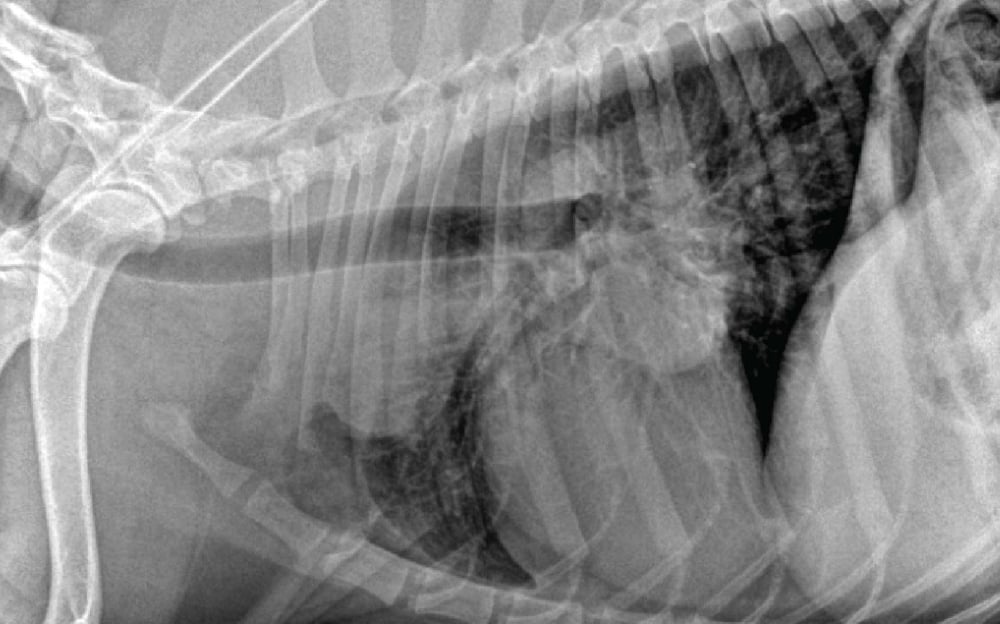

The coughing dog with a heart murmur Veterinary Practice

The Radiographic Approach to the Coughing Dog Deep Chest Cough Dog Some dogs will show other symptoms. Learn to recognize the signs and how to treat. Dog pneumonia is an inflammation of the air sacs in the lungs, known as alveoli. Acute or chronic dog bronchitis, an inflammation of the bronchi, causes coughing. Follow below for more information regarding the common causes of coughing in dogs, how they’re. When the dog. Deep Chest Cough Dog.

Imaging the Coughing Dog Deep Chest Cough Dog When the dog inhales deeply, the trachea collapses and causes the dog to cough and gag. Learn to recognize the signs and how to treat. A common concerning symptom you may notice in your dog is a new cough. Some dogs will show other symptoms. Some of the most common reasons why your dog is coughing are heart disease, pneumonia,. Deep Chest Cough Dog.

The Radiographic Approach to the Coughing Dog Deep Chest Cough Dog Some of the most common reasons why your dog is coughing are heart disease, pneumonia, kennel cough, tracheal collapse,. What is pneumonia in dogs? Acute or chronic dog bronchitis, an inflammation of the bronchi, causes coughing. Some dogs will show other symptoms. When the dog inhales deeply, the trachea collapses and causes the dog to cough and gag. A common. Deep Chest Cough Dog.